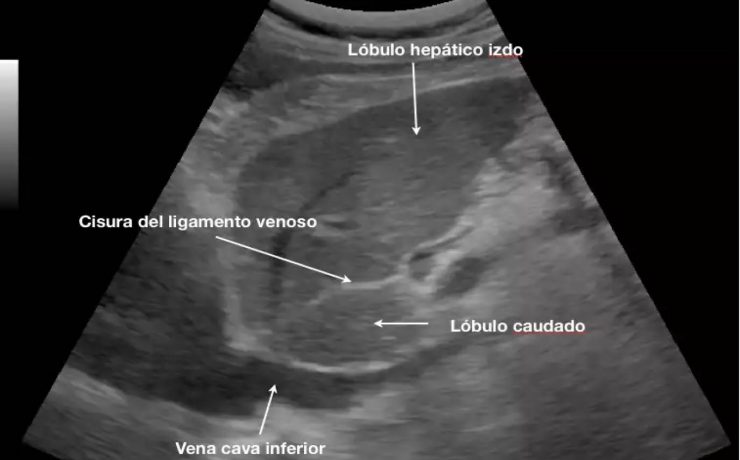

El signo del lirio caído , fue descrito hace más de 40 años en pielografía de eliminación y corresponde al aspecto que adquiere el sistema pieloureteral inferior en un riñón con doble sistema excretor, dado por una pelvis renal de orientación horizontal y cálices que se dirigen discretamente hacia cauda.